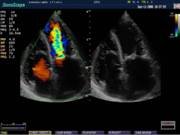

Компания SonoScape уделила особое внимание допплеровским режимам и является экспертом в своем классе, что позволяет с легкостью, но в то же время с уникальной точностью проводить исследования с постановкой наиболее точного диагноза.

Ультразвуковые исследования, доплеровское сканирование сосудов в Центре современных медицинских технологий «АКВА МЕД МАРИН» выполняется при помощи первого и единственного аппарата в Керчи SonoScape S40Exp (экспертного класса, который оснащен множеством новейших функций, многократно улучшающих качество и информативность УЗИ-исследования).